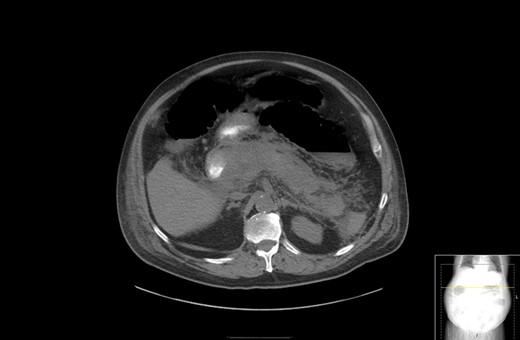

A 67-year-old male presented to his local hospital with postprandial right upper quadrant (RUQ) abdominal pain and vomiting. CT scan of the abdomen and pelvis with oral contrast showed extensive stranding and ill-defined fluid attenuation surrounding his pancreas (Fig. 1). Initial serum amylase and serum lipase levels were 2918 and 17 360, respectively. He was diagnosed with acute, necrotizing, gallstone pancreatitis and developed gastric outlet obstruction (GOO) 9 days after the onset of his symptoms, at which time he was transferred to our institution for further care. On arrival, he had GOO and renal failure (creatinine 2.1 mg/dl). A gastro-jejunal (GJ) feeding tube was placed for jejunal feeds and gastric decompression. On hospital Day 7, the patient’s pain had resolved and a cholecystectomy was attempted laparoscopically, but was converted to open due to inflammation around the infundibulocystic junction. Subsequently, a follow-up contrasted CT showed marked interval necrosis of pancreatic tissue resulting in numerous lobulated soft tissue and gas collections in the upper abdomen, midline upper pelvis, and in the gallbladder fossa (Fig. 2). A pancreatic drain was placed by interventional radiology (IR) on hospital Day 20 for interval increase in pancreatic necrosis on CT. On hospital Day 23, IR embolization of gastroduodenal artery (GDA) was performed due to GI bleeding. Laparoscopic necrosectomy with malencot drain placement was performed on hospital Day 36. Post-operatively, he had a large upper GI bleed requiring emergent endotracheal intubation and initiation of the massive transfusion protocol. Angiography was performed and was negative. On the following day, hospital Day 39, GI performed an EGD and found hemorrhagic gastritis, but no localizable bleeding. He was placed on high dose PPI, carafate and octreotide. He progressed to acute renal failure with initiation of hemodialysis on hospital Day 45. On hospital Day 47, a follow-up EGD was done with exchange of the gastrojejunostomy tube, and hemorrhagic gastritis was still present. He was transferred to the general surgery inpatient unit the following day. On hospital Day 54, he developed another upper GI bleed requiring ICU transfer. EGD was again performed and the hemorrhagic gastritis remained, but no active site of bleeding was identified. On hospital Day 56, a second look EGD was done with similar findings of hemorrhagic gastritis with no identifiable active bleeding. On hospital Day 58, the patient elected to receive palliative care rather than undergo subtotal gastrectomy. He died 9 days later at home.

CT with oral contrast showing extensive stranding and ill-defined fluid attenuation surrounding his pancreas.